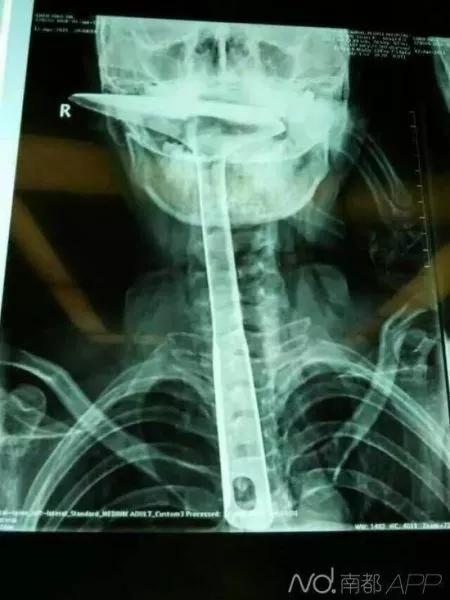

2015年5月,东莞虎门陈师奶,因喉咙难受将30公分的炒菜锅铲插进食道,结果导致食道表皮粘膜损伤严重,且被捅破了一个洞!